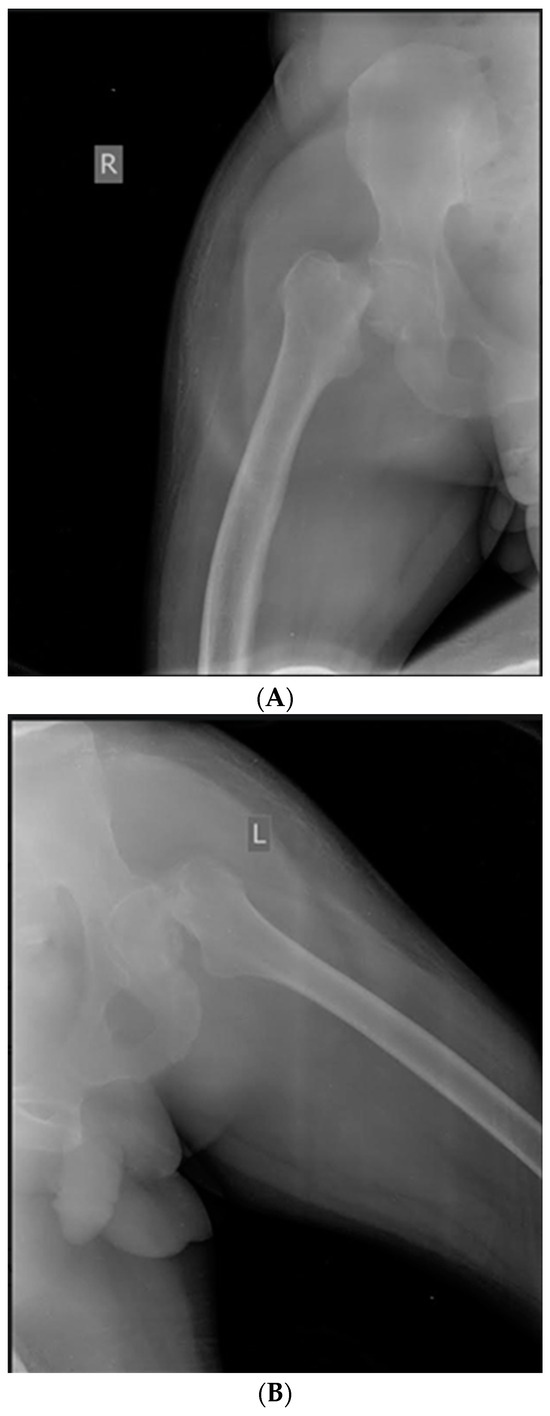

Case 1. Femoral neck fractures are common in the elderly population, who are frequently confronted with osteoporosis. Though rare, these fractures can also occur, mainly unilaterally, in younger individuals following a high-energy trauma. Only a few articles describe bilateral simultaneous femoral neck fractures as an injury resulting from seizures, and these were not assessed in PwH. We report a case of a bilateral femoral neck fracture in a 50-year-old male with severe haemophilia B (SHB) following a generalized convulsion. The patient was addressed to the emergency department for a generalized tonic-clonic seizure episode, and the patient was known and had been treated for epilepsy; he presented with evidence of SHB and multiple haemophilic arthropathies without a history of trauma or any comorbidities. On examination, the lower limbs were externally rotated; there were no distal neurovascular deficits, open wounds, or trauma evidence. Radiography revealed a bilateral femoral neck fracture (Figure 1A,B). Under rigorous hemostatic control, the orthopaedic surgeon team decided to intervene in one stage, and bilateral simultaneous hip arthroplasty was performed. The right hip joint was complicated with pertrochanteric fracture and needed additional osteosynthesis with screws (Figure 1C). Postoperatively, bedside hip range of motion exercises were started within days 2–3 after surgery, continuing with an enhanced rehabilitation program. The patient had a favourable outcome without any post-operative complications and was discharged after 30 days. Overall costs were EUR 86,856.05, and the factor concentrate accounted for 91.75% of expenditures (recombinant FIX, ~EUR 79,697.48). However, these two simultaneous major interventions had a decisive, favourable effect on the costs and rehabilitation of the patient. Due to a forceful contraction of muscles during an episode of generalised tonic-clonic seizures, a fracture or dislocation may develop.

Figure 1.

(A) Case 1—X-ray: Right femoral neck fracture—before surgery. (B) Case 1—X-ray: Left femoral neck fracture—before surgery. (C) Case 1—X-ray: Bilateral simultaneous hip arthroplasty, the right hip joint was complicated with pertrochanteric fracture and needed additional osteosynthesis with screws.